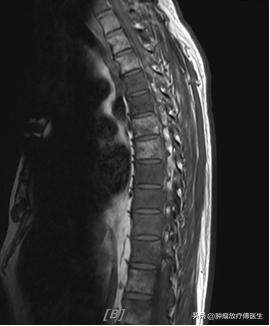

2015年10月29日我院泌尿外科行经尿道前列腺电切术,术后病理示前列腺腺泡腺癌,Gleason评分5+4=9。术后恢复可,期间出现全身酸痛,2015年11月17日查骨ECT示全身多发骨(颅骨、脊柱、骨盆、双侧肋骨、胸骨、双侧肩胛骨、左侧肱骨、双侧股骨)放射性异常浓聚。2015年11月27日行盆腔MRI报告:前列腺外周叶及中央叶多发结节样异常信号,结合病史,考虑前列腺癌。行胸、腰椎MRI平扫+增强:胸、腰椎体、双侧髂骨及所见双侧股骨多发结节状异常信号影,考虑转移灶。

2015年12月1日、12月22日2016年1月12日、2016年2月2日、2016年2月24日、2016年3月16日行“多西他赛120mg 次/21天”方案化疗6周期,过程顺利。第四周期化疗后,2016年2月24日复查盆腔MRI示现前列腺病灶体积较前2016年1月11日MRI大致相仿,多发骨转移与前大致相仿,淋巴结较前大致相仿。胸椎、腰椎MRI检查示胸腰椎体、双侧髂骨及所见双侧股骨多发结节状异常信号影,较前2015年11月26日片大致相仿,考虑转移灶。行ECT(骨关节)检查提示(图41-3)全身多发异常核素浓聚灶,考虑肿瘤骨转移,放射性浓聚较前变淡,提示治疗有效。

2016-1-11胸椎MR